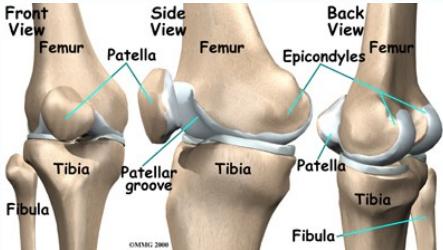

Knee Anatomy